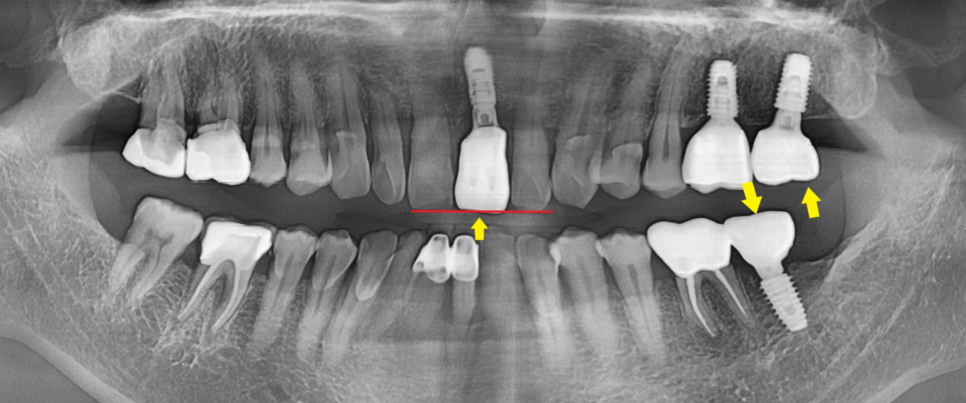

기존 치아 상태와 뼈 상태를 확인하는

파노라마 엑스레이를 촬영하여 보니

상악 좌측 중절치는

치아가 아래로 많이 내려와 있는 상태로

발치 후 임플란트가 필요하신 상황이었고,

상악 좌측 제2대구치와

하악 좌측 제2대구치가 없으셔서

오른쪽으로만 식사하시는 상황이었습니다.